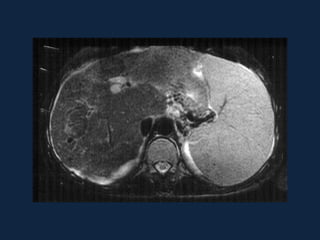

Hiperplasia Nodular Focal

► s/c: lesão bem delimitada, homogênea isodensa ou

discretamente hipodensa.

► c/c: realce intenso, precoce e fugaz.

– Fase arterial: acentuado realce homogêneo, exceto pela cicatriz

central.

– Fase portal: hipo ou isodensa ao parênquima hepático. Início do

realce da cicatriz.

– Fase tardia: isodensa ao parênquima hepático, com realce da

cicatriz.